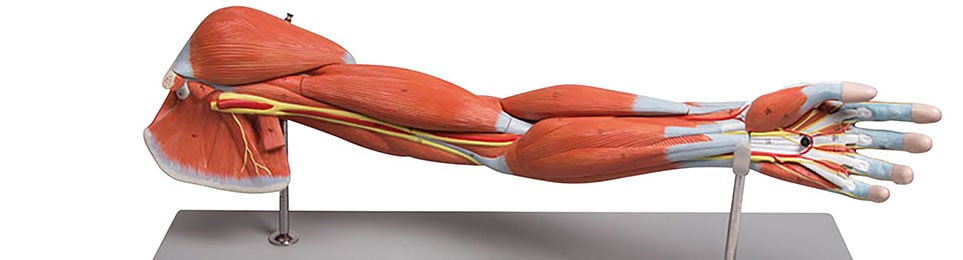

Anatomical Models

Anatomical models as teaching aids

Anatomical and medical models are perfect teaching aids to show and explain the different structures of the human body and the different functions of the joints, muscles, vertebrae, etc.

Medical students and trainees in health care as well as doctors, professors, lecturers, physiotherapists and many health service providers work with the various anatomical models. Due to the realistic, human and life-size presentation, the added value of these medical models is particularly great. As a teaching aid, the anatomy models help enormously to understand the structure and functions of the human body. As part of patient education, the models help the treating doctor or therapist to clearly explain the symptoms and the subsequent treatment to his patient. The visual demonstration helps the patient to understand the important details and thus promotes the relationship of trust between the doctor or therapist and the patient.

Our anatomical models are casts of real samples that are manufactured in accordance with medical quality standards. This gives you models made of high-quality materials that are not only helpful, but also very durable.

In our Kübler Sport range you will find the following anatomical models: